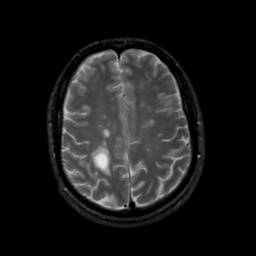

MR Study #8, March 31, 1991 -- Slice #36